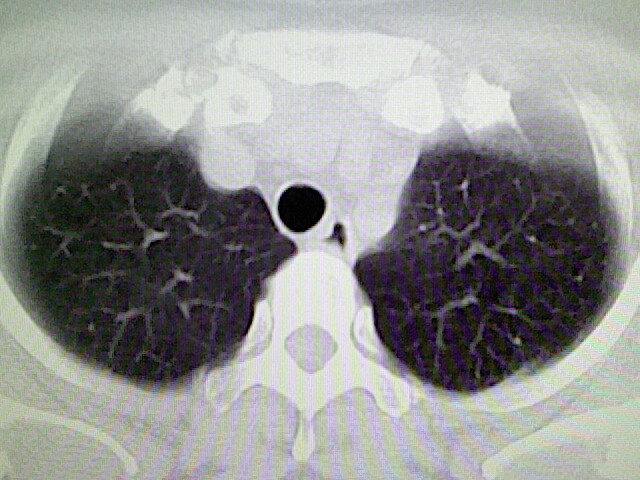

女,52岁,咳嗽,咳痰多日

左下肺陈旧纤维索条!

左肺舌段炎性改变

我见过几例,为炎症后纤维条索

慢性炎症后改变

考虑慢性炎性病灶粘连牵拉改变。

左肺舌叶纤维锁条病变。

左肺上叶下舌段炎症并局部胸膜反应。

左肺舌叶纤维索条影。

左肺舌叶段陈旧性病变

左肺舌段炎性反应。片子的质量太不好了。

左肺舌段炎性

炎性改变

左肺舌叶纤维索条影